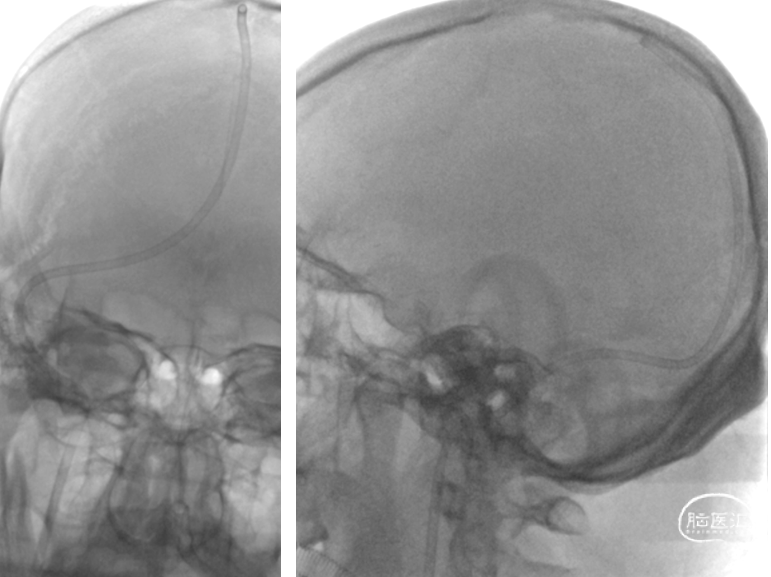

DSA(2022-1-6)

右侧颈总动脉造影示:上矢状窦显影模糊,右侧横窦、乙状窦未见显影,静脉回流缓慢。穿刺右侧颈静脉,留置8F血管鞘,全身肝素化,50万尿激酶入动脉滴注。

术前DSA